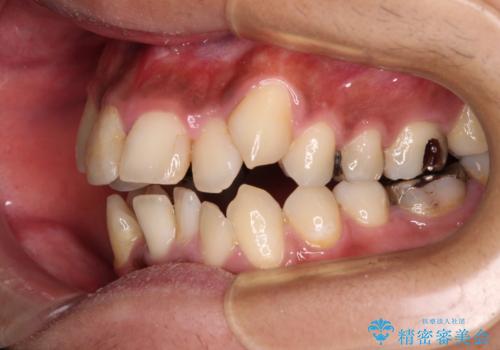

八重歯と開咬 ワイヤー装置での抜歯矯正

- 前歯のデコボコと八重歯、開咬を気にして来院された患者様です。

骨格的に下顎骨が上顎骨に対して後退位であったため、上顎の左右第一小臼歯を抜歯し、デコボコを改善するとともに開咬を改善していくこととしました。

舌の突出癖により開咬となっていたため、突出癖改善のためのトレーニングをしっかりと行っていただき、予定の期間で無事に治療を終えることができました。